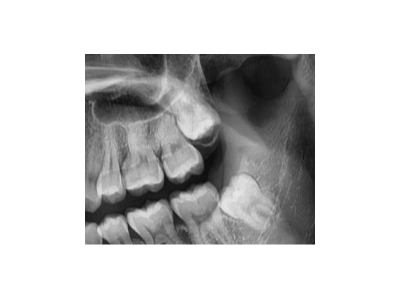

實(shí)際上,牙齒松動(dòng)都是一個(gè)值得關(guān)注的口腔問(wèn)題。那么,牙齒松動(dòng)還能好嗎?答案是視情況而定。一、牙齒松動(dòng)的原因牙周炎這是導(dǎo)致牙齒松動(dòng)常見(jiàn)的原因之一。牙周炎是由牙菌斑中的細(xì)菌引起的慢性感染性疾病,會(huì)導(dǎo)致牙齦發(fā)…